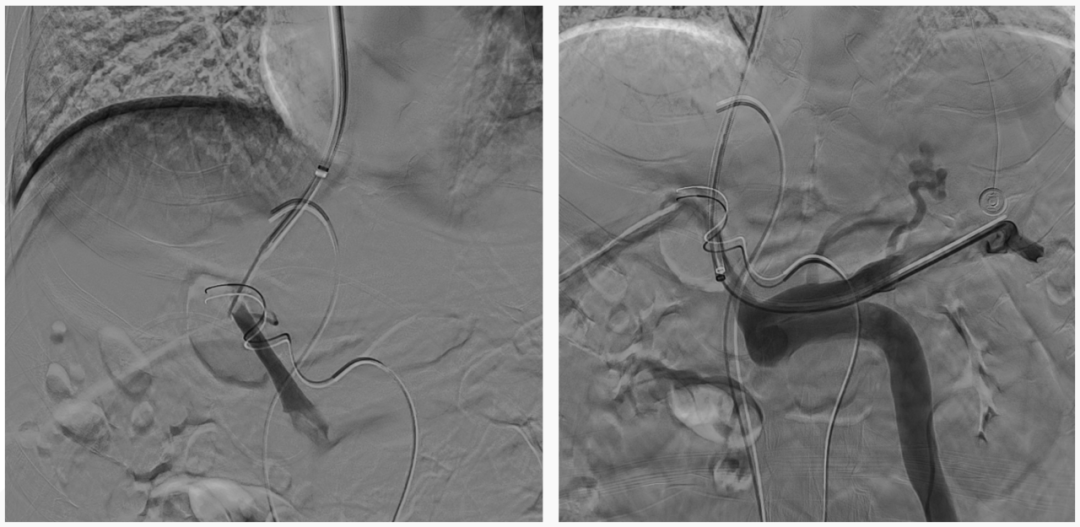

超選至腸系膜下靜脈異常分流道,予以栓塞18mm的Amplatzer vascular plug及適量25%生物膠,造影示異常分流道消失

8mm覆膜支架釋放于肝內(nèi)穿刺道,考慮門脈纖細,遂以6mm球囊后擴張

異常分流道栓塞后,再次行門靜脈造影,血流呈向肝狀態(tài),食管胃底曲張靜脈較前更顯著,微導管超選至曲張的胃冠狀靜脈,予以彈簧圈及25%生物膠栓塞,造影示曲張靜脈消失,肝內(nèi)門脈顯影較術(shù)前顯著改善